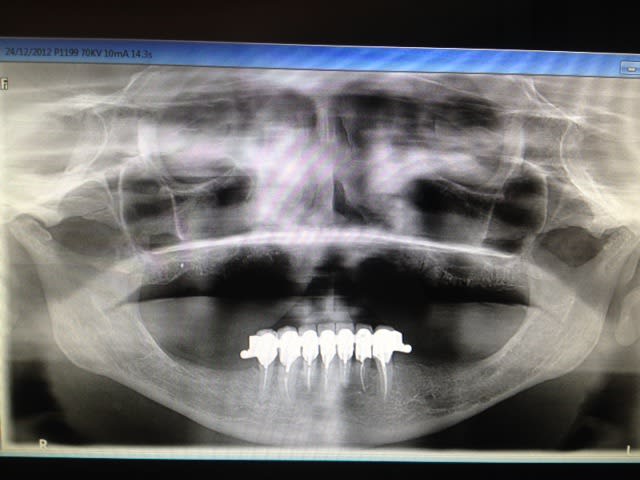

max sup à réaliser en septembre

basale obligatoire !